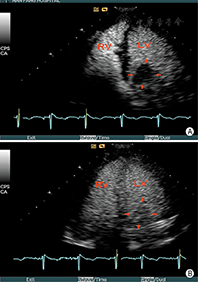

②左心室心尖肥厚:7%肥厚型心肌病为心尖明显肥厚。常规超声心动图检查因不能完整清晰显示心尖,将使15%心尖肥厚型心肌病漏诊。当怀疑是心尖肥厚型心肌病而不能被明确或排除时,应该进行心脏造影检查(图4)。心尖肥厚型心肌病左心室心腔轮廓的典型造影表现为左心室腔呈"铲子样" (spade-like)的外观,心尖部室壁明显增厚(图5);在心尖肥厚型心肌病中肥厚的心尖部造影剂灌注通常是相对减少的,与心腔内的高强度造影剂形成明显的对比[25]。

③左心室心肌致密化不全:心肌致密化不全是一种罕见的、但是越来越多地被临床认识的疾病,可导致心力衰竭、心律失常、血栓栓塞事件和死亡。室壁由增厚的运动减弱的两层心肌组成:较薄的致密化心外膜下心肌和较厚的非致密化心内膜下心肌。当怀疑左心室致密化不全,但传统的二维超声成像不能清晰显示窦隙状非致密化心肌时,造影超声心动图检查可显示突入左心室腔肌小梁之间的血池内有造影剂填充[26,27,28](图6,图7)。采用MI 0.3~0.5谐波成像,有助于更清楚显示肌小梁间隐窝。目前,孤立性左心致密化不全的诊断标准尚未统一,但通过超声造影显示非致密化心肌厚度与致密化心肌厚度比值> 2时有助于该病的确诊。